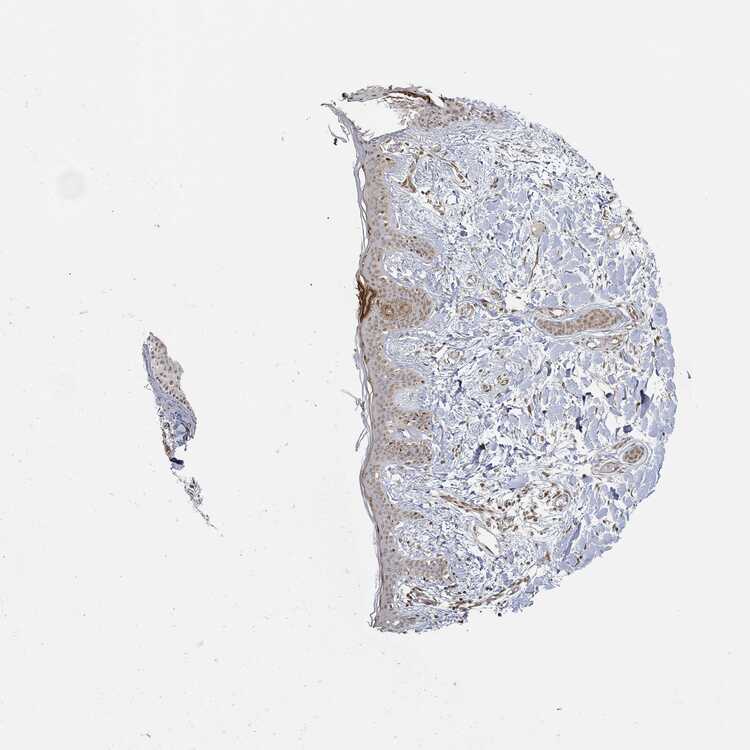

SKIN 1 - Antibody stainingi

Antibody staining in the annotated cell types in the current human tissue is reported as not detected, low, medium, or high, based on conventional immunohistochemistry profiling in selected tissues. This score is based on the combination of the staining intensity and fraction of stained cells.

Each image is clickable and will lead to virtual microscopy that enables deeper exploration of all samples and also displays staining intensity scores, fraction scores and subcellular localization as well as patient and tissue information for each sample.

Antibody HPA042413Antibody HPA074310Antibody CAB012991

Langerhans Not detectedMediumLow

Fibroblasts Not detectedMediumLow

Keratinocytes Not detectedLowMedium

Melanocytes Not detectedMediumLow

SKIN 2 - Antibody stainingi

Epidermal cells Not detectedMediumMedium